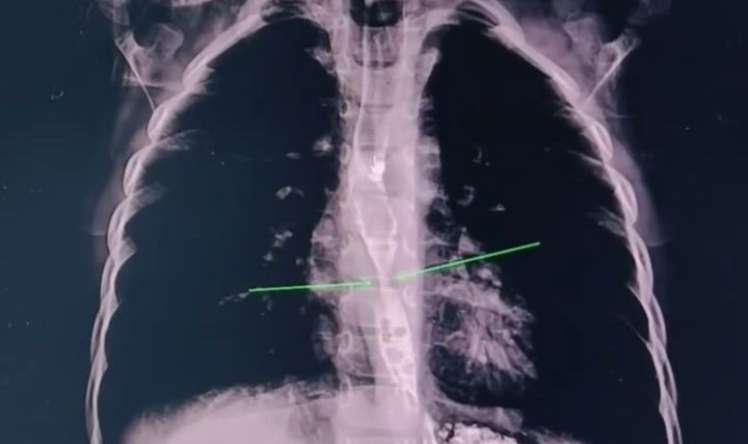

Ateroskleroz (damar tutulması) geri dönməz proses deyil. İnteqrativ yanaşma – düzgün qidalanma, hədəfli nutrisevtik dəstək və toksinlərdən təmizlənmə vasitəsilə damar yaşlanmasını ləngitməyə və mövcud tıxanıqlığı stabilləşdirməyə imkan verir.